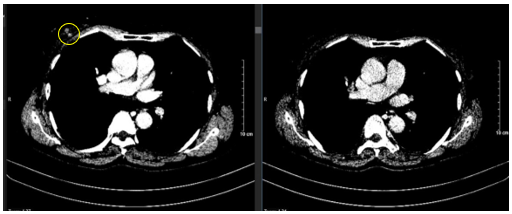

- Cắt lớp vi tính lồng ngực: Không phát hiện tổn thương tổn thương phổi bất thường. Vú phải có nốt ngấm thuốc vị trí 12 giờ-13 giờ, kích thước 10x12mm.

Hình 5: Hình ảnh cắt lớp vi tính lồng ngực: Hình ảnh vú phải có nốt ngấm thuốc vị trí 12 giờ -13 giờ, kích thước 10x12mm (mũi tên màu vàng).

- Cắt lớp vi tính lồng ngực: Không phát hiện tổn thương bất thường. Không còn Nốt ngấm thuốc trước điều trị.

Hình 7:

Hình ảnh so sánh phim chụp cắt lớp vi tính lồng ngực trước điều trị (bên trái) và sau điều trị tân bổ trợ 6 chu kỳ (bên phải). Nốt ngấm thuốc ngực phải trước điều trị (hình tròn màu vàng) đã biến mất hoàn toàn.